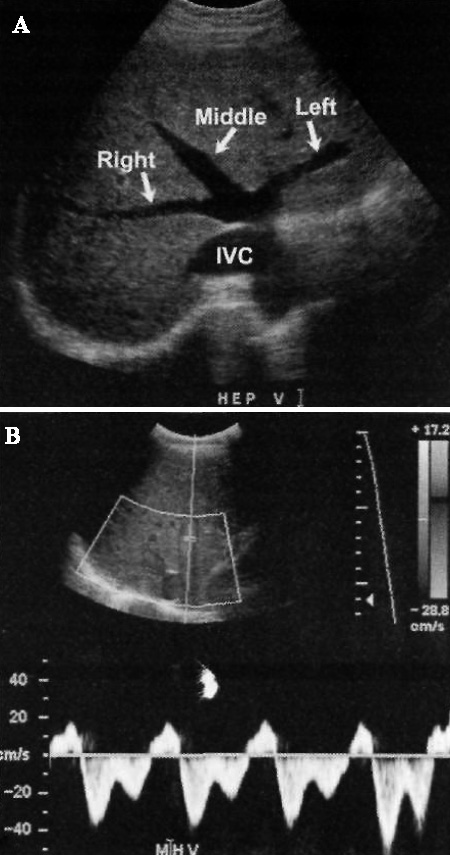

Печеночные вены делятся на правую, среднюю и левую; в некоторых случаях есть добавочная правая вена печени. Средняя и левая печеночные вены, как правило, имеют общий короткий ствол. Эти сосуды являются анатомическими ориентирами для проведения сегментарной резекции печени с целью донорской трансплантации. В норме кровоток состоит из трех фаз, отражающих сердечную активность. В систолу и диастолу желудочков сердца кровоток направлен вперед, в момент систолы предсердий отмечается незначительное обратное движение. У больных с циррозом печени наблюдается монотонный (приглушенный) кровоток, а из-за сдавления вен паренхимой могут возникнуть трудности с их обнаружением. Чтобы выявить вены, которые не визуализируются на УЗИ в режиме серой шкалы, применяют метод цветовой допплерографии (фото 3).

Допплерография: Печеночные вены

Фото 3. Печеночные вены в норме. А – ультразвуковое изображение в режиме серой шкалы демонстрирует нормальное соотношение печеночных вен. В – спектральная допплерограмма демонстрирует нормальный венозный кровоток печени